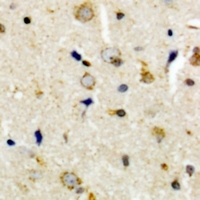

- Immunohistochemical analysis of CEP135 staining in human brain formalin fixed paraffin embedded tissue section. The section was pre-treated using heat mediated antigen retrieval with sodium citrate buffer (pH 6.0). The section was then incubated with the antibody at room temperature and detected with HRP and DAB as chromogen. The section was then counterstained with hematoxylin and mounted with DPX.